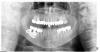

talshik Опубликовано 13 июля, 2011 Поделиться Опубликовано 13 июля, 2011 (изменено) Пациент 82 года рождение,жалобы на неприятный запах изо рта,прорезание имплантата через слизистую.Срок службы протеза 1 год.Имплантат Новокузнецк.Когда удалял имплантат он хорошим словом вспомнил Новокузнецк,хирурга который ставил имплантат и конечно же ортопеда.Как обычно почти весь пророс соединительной тканью.Мягких тканей как обычно не хватило,в натяжении было,на всякий случай поставил мембрану.Ширина кости уж точно 5-6 мм есть,можно было спокойно ставить норм имплантат.След.процедура через мес костный блок ввиде накладки.Вот снимок.Завтра покажу фото самого имплантата.Вот вам и Новокузнецк. Изменено 13 июля, 2011 пользователем talshik Ссылка на комментарий